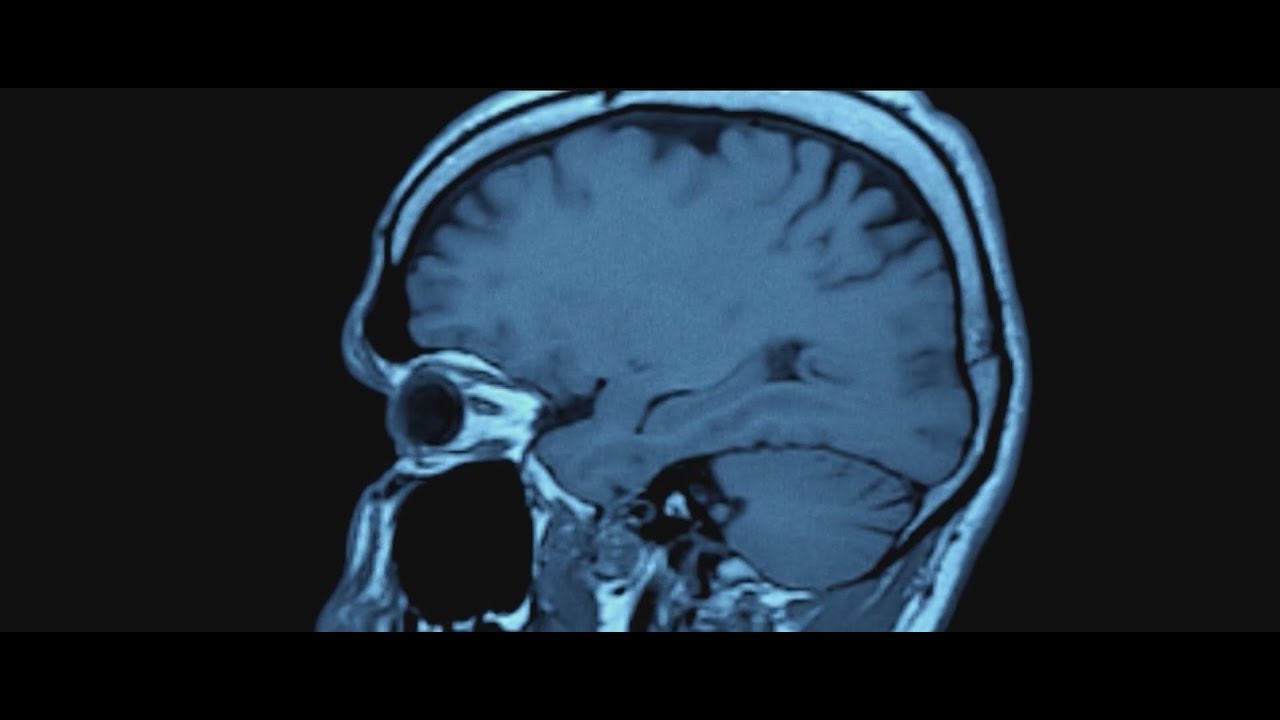

nflnewsbyzennie62.com Presents:Park Avenue shooter targeting the NFL had CTE: Medical examiner

. A vlog by the YouTube channel named in the video’s upper left corner and serves as the original blog post for this content.The man who shot and killed four people inside 345 Park Ave. in July had Chronic Traumatic Encephalopathy, also known as …

Manhattan shooting latest: Gunman mentioned CTE, appeared to target NFL ABC News - Breaking News, Latest News and Videos

NYC office shooter had low-level CTE, medical examiner finds BBC

NYC shooter Shane Tamura had CTE, medical examiner says NBC News

Gunman Who Attacked Midtown Office Building Had C.T.E. The New York Times